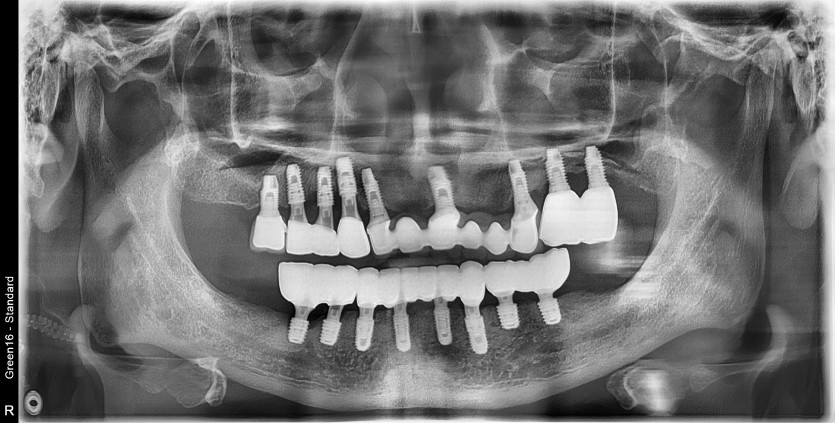

만 56세 하악 전체 임플란트 증례(상악 일부)

하악 전체 임플란트 증례입니다.

11개의 임플란트로 완성하였습니다.